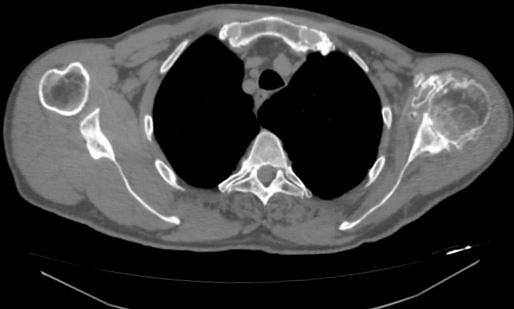

Purpose Segmentation of rheumatoid joints from CT images is a complicated task. The pathological state of the joint results in a non-uniform density of the bone tissue, with holes and irregularities complicating the segmentation process. For the specific case of the shoulder joint, existing segmentation techniques often fail and lead to poor results. This paper describes a novel method for the segmentation of these joints. Methods Given a rough surface model of the shoulder, a loop that encircles the joint is extracted by calculating the minimum curvature of the surface model. The intersection points of this loop with the separate CT-slices are connected by means of a path search algorithm. Inaccurate sections are correct ed by iteratively applying a Hough transform to the segmentation result. Results As a qualitative measure we calculated the Dice coefficient and Hausdorff distances of the automatic segmentations and expert manual segmentations of CT-scans of ten severely deteriorated shoulder joints. For the humerus and scapula the median Dice coefficient was 98. 9% with an interquartile range (IQR) of 95 .8% -99. 4% and 98. 5% (IQR 98 . 3% - 99. 2%) respectively. The median Hausdorff distances were 3.06 mm (IQR 2.30 mm - 4.14 mm) and 3.92 mm (IQR 1.96 mm - 5.92 mm) respectively.